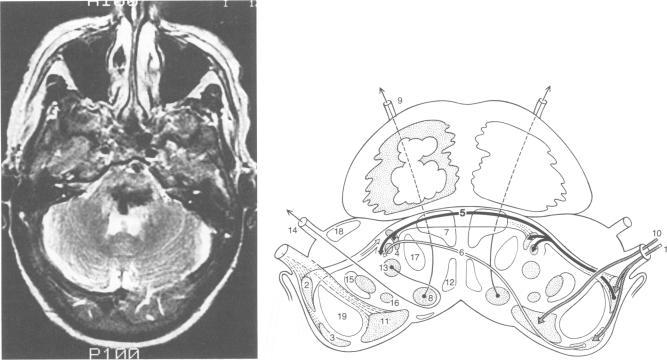

A 64 year old woman with a predominantly midline pontine tegmental haemorrhage presented with bilateral total deafness. One week later reasonable pure-tone thresholds appeared but she still had total bilateral loss of speech discrimination. At that time contralateral acoustic reflexes were bilaterally absent, whereas ipsilateral acoustic reflexes and waves IV and V of the brainstem auditory evoked potential were bilaterally preserved. It is proposed that this patient's hearing deficit was due to inactivation of the ventral acoustic striae decussating in the trapezoid body. This case supports the contention that in humans the ventral pontine acoustic decussation carries most of the neural signals required for hearing and perhaps all the neural signals required for speech perception.